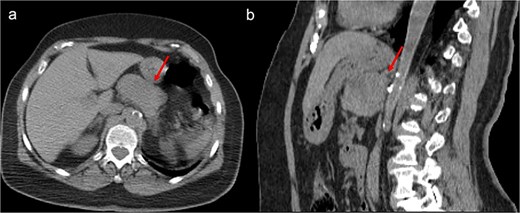

A thoraco-abdominopelvic computed tomography (CT) scan performed for staging revealed a well-defined, homogeneous soft-tissue mass anterior to the celiac trunk, superior to the pancreas, and medial to the stomach (Fig. 1). A positron emission tomography (PET) scan confirmed the previously known hypermetabolic retroareolar lesion of the right breast and revealed a large hypermetabolic mass in the celiac–mesenteric region, measuring 63 × 35 × 50 mm (Fig. 2). An abdominal MRI characterized the mass as a well-defined 6-cm lesion with mixed solid and cystic signal intensity, closely related to the celiac trunk, pancreas, stomach, and left adrenal gland (Fig. 3). Biochemical testing showed elevated urinary normetanephrine and metanephrine levels, consistent with catecholamine hypersecretion.

Unenhanced CT scan, axial (a), and sagittal reconstruction (b), revealing a well-defined oval mass with regular contours and soft-tissue density, closely contacting the posterior wall of the stomach and appearing to occupy the omental bursa. The lesion does not invade adjacent structures.